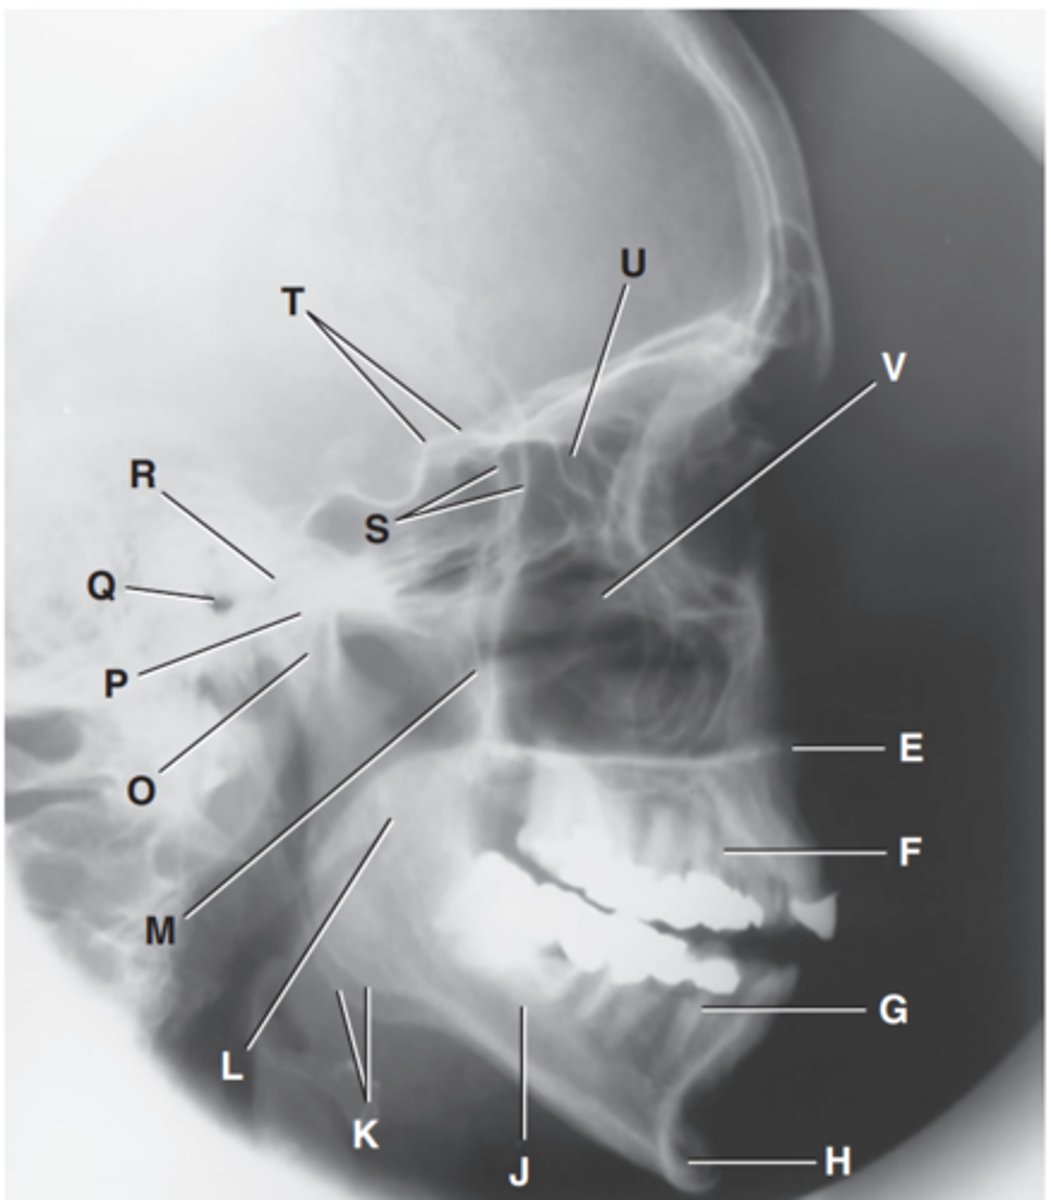

Greater wings of sphenoid

Label S

Lesser wings of sphenoid with anterior clinoid processes

Label T

Ethmoid sinuses between orbits

Label U

Body of maxilla containing maxillary sunuses

Label V